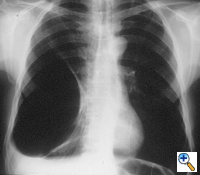

| Figure 3: Chest x-ray of a large bulla with true infection; after the appropriate medical treatment fever, hemptysis and fluid level persisted and the bulla was resected. |